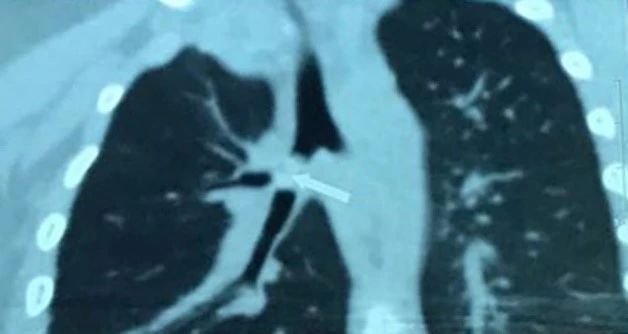

下午接诊一例鼻出血患者,经门诊多次填塞止血后仍有出血,考虑随时有鼻出血加重可能,外科医生与我们协商后决定全麻下为患者行鼻内镜下止血术。患者坐在候诊区,低着头不断地擦拭着吐出的血性液体,家属不安地站在身旁。仔细询问病史,患者告诉我: “出了好多次血了”; “这两天我吃也吃不下,睡也睡不好”; “昨天晚上开始就没吃任何东西了,吃不下”。 看着病人惴惴不安的样子,我只能轻声安慰“会好起来的”。考虑患者清醒合作,咽下血性液体不多,决定行喉罩下全身麻醉。患者入手术室后,心电监护下予面罩吸氧,开放静脉,备好吸引设备,经充分去氮给氧后快速静脉诱导,置入双管喉罩后行控制通气和胃肠减压。手术历时80分钟,喉罩通气良好,清除口腔内残留的血液,充分镇痛下待患者恢复自主呼吸,配合指令动作后拔除喉罩。 本以为这个值班就这样过去了,清晨6点拷机忽然响起,被告知有一例13月龄的小儿气道异物,来不及洗漱我就冲到楼下,准备好药物及紧急气道插管工具。 患儿由父母和爷爷抱到等待室,即使在妈妈的怀里,眼中仍充满了不安。妈妈一边流泪一边诉说着病史,昨天姐姐抱着弟弟玩,爷爷给他们喂板栗,难得回一次老家,大家特别高兴。突然姐弟俩摔了一跤,弟弟含着一嘴的板栗哇哇大哭,妈妈赶紧跑过去抠出儿子口中的板栗,但孩子仍然被呛得不停地咳嗽,午后孩子不但频繁咳嗽,还喘得厉害。家长带着他一路从当地县中心医院、市医院辗转到上海儿童医院,最后凌晨3点赶到我们医院。 (患儿术前CT片) 患儿近期患幼儿急疹已愈,既往有湿疹史,对多种食物过敏,听诊右上肺无呼吸音,左肺稍许哮鸣音,我们讨论后决定保留呼吸下经支气管镜行气道异物取出术。二线医生把患儿抱入手术室坐在怀里,吸着麻醉药慢慢入睡,开放静脉后我们使用静脉药物成功保留住了自主呼吸,整个手术过程中,患儿自主呼吸平稳,氧供充分,为外科医生提供了良好的手术条件。其实,板栗这样的气道异物,对外科医生来说难度颇大,钳子一夹“泡软的”板栗就碎了,非常难取,但是在主刀医生的不懈努力下还是把堵塞的气道清理干净了。 (异物——“泡软”的板栗) 术后我们置入了一枚双管喉罩,等待患儿苏醒。这时接班医生来了,由于气道异物患儿的苏醒期仍有发生突发事件的风险,我们不放心走,四个麻醉医生一起围坐在孩子身边。看着他睁开眼睛找妈妈,我们悬着的一颗心也放了下来。